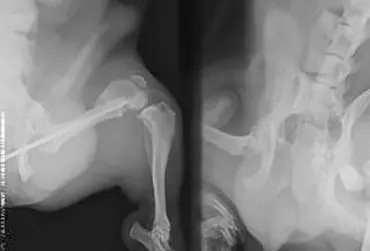

Wykorzystanie autogenicznego przeszczepu istoty gąbczastej i płyty L blokowanej w zabiegu korekcyjnym osteosyntezy kości udowej – opis przypadku

Opisywany przypadek dotyczy 4-letniego psa, samca, rasy pekińczyk. W innym zakładzie leczenia zwierząt wykonano zabieg osteosyntezy lewej kości udowej za pomocą pojedynczego gwoździa śródszpikowego. Pacjent trafił do przychodni w celu konsultacji ortopedycznej z powodu braku efektów leczenia. Badanie radiologiczne uwidoczniło przebudowę kości udowej oraz wytworzenie stawu rzekomego z miejscu przełomu. Wykonano zabieg osteosyntezy z użyciem płyty L blokowanej 2,7 mm oraz przeszczepu istoty gąbczastej z kości ramiennej.